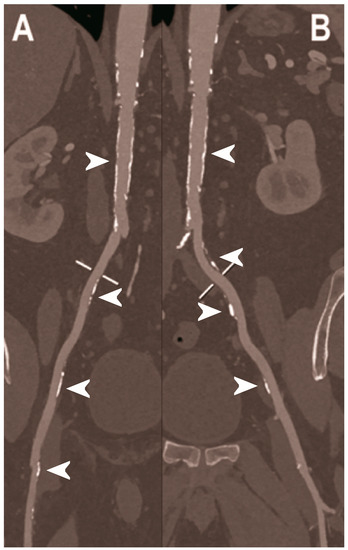

Figure 6.

Abdominal CT angiography using photon-counting computed tomography. The figure shows advanced multiplanar reconstructions without and with MIP algorithm of a distal abdominal aorta and ilio-femoral arterial axes derived from a photon-counting CT (Scanner: NAEOTOM Alpha, Siemens) acquisition (A,B right; C,D left). The projection start in the abdominal aorta carrefour and end in the right/left common femoral artery. There are massive calcifications along the common iliac arteries; however, both MPRs (A,C) and MIPs (B,D) are so sharply defining the edges of the structures that lumen assessment is not compromised (arrowheads).

Figure 7.

Abdominal CT angiography using photon-counting computed tomography. The figure shows advanced multiplanar reconstructions of an abdominal aorta and ilio-femoral arterial axes derived from a photon-counting CT (Scanner: NAEOTOM Alpha, Siemens) acquisition (A,B). In (A) the projection starts in the abdominal aorta at the level of thoraco-abdominal junction and ends in the right common femoral artery while in (B) it ends in the left common femoral artery. While there are significant calcifications along the vessels (arrowheads in A and B), the vessel wall is so sharp that the fact that there is no lumen reduction appears to be quite natural as compared to the common blooming effect seen with conventional energy-integrating detectors.